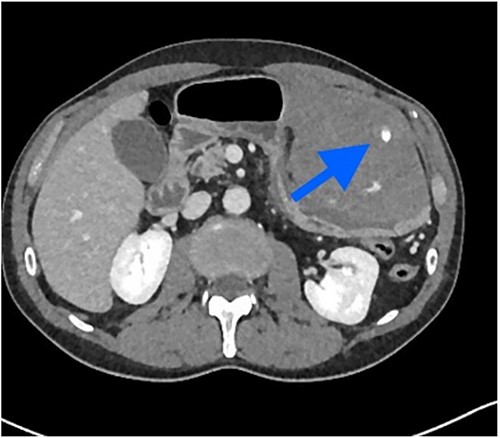

Non-contrast abdominal computed tomography (CT) revealed hemoperitoneum: moderate ascites with organized clot on the surface of greater omentum (Fig. 1)

Computed tomography image on admission: moderate ascites with organized clot.